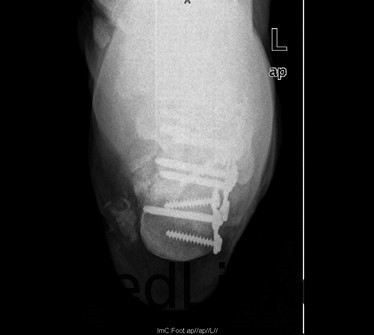

患者男,37岁,因“外伤后双足跟疼痛、肿胀伴腰痛11+天”入院。患者11+天前和工友施工时不慎从二楼摔下,双足跟着地,当时即感双足剧烈疼痛,踝关节活动障碍,伴腰背部疼痛,左足跟长约3厘米伤口,患者诉可见骨断端外露,伤后2小时患者被送往当地人民医院,急诊行清创缝合术,术后给予输液、抗炎、消肿等对症治疗,双足水肿减轻,患者为求诊治进一步诊治来我院,急诊以双足跟骨折收住我科。

查体:双足中度肿胀,左足跟底内侧长约3cm清创缝合术后伤口,伤口干燥,无红肿渗液,双足背、足底、双踝关节中度肿胀,双足皮温正常,足背动脉正常扪及,双下肢肌力五级,双足趾活动正常,双踝关节疼痛活动受限。 辅查:双足X线示:双足跟粉碎性骨折,关节面塌陷。

初步诊断:1、右跟骨粉碎性骨折2、左跟骨粉碎性开放性骨折清创缝合术后 诊疗计划:拟行双侧跟骨切开复位植骨、钢板、螺钉内固定术+髂骨取骨术